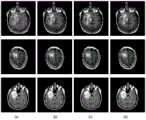

图4TCGA数据集的低级胶质瘤MR图像和分割掩膜示意图:Figure 4 Schematic diagram of the low-grade glioma MR image and segmentation mask of the TCGA dataset:

(a)pre-contrast;(b)FLAIR;(c)post-contrast;(d)ground truth;(a) pre-contrast; (b) FLAIR; (c) post-contrast; (d) ground truth;

图5cGAN生成的人工低级胶质瘤图像:Figure 5 Artificial low-grade glioma image generated by cGAN:

实验使用的影像数据来自美国国家癌症研究所赞助的癌症影像档案(The CancerImaging Archive,TCIA),其中包含癌症基因组图谱(The Cancer Genome Atlas,TCGA)患者对应的MR影像。从TCGA-LGG集合中选取110例患者,其影像数据分别来以下自5个机构:Thomas Jefferson University(TCGA-CS,16例),Henry Ford Hospital(TCGA-DU,45例),UNC(TCGA-EZ,1例),Case Western(TCGA-FG,14例),Case Western St.Joseph’s(TCGA-HT,34例)。所选100例患者包括51例II级胶质瘤,58例III级胶质瘤,1例肿瘤的分级未知。所选数据包括前对比(pre-contrast)、FLAIR和后对比(post-contrast)三个序列,如图4所示,(d)为手工分割掩膜。随机选取10例患者作为测试集,100例患者作为训练集,每例患者的术前影像切片数量在20~88之间不等,包含含瘤切片和不含瘤切片。在同一个病人MR图像集中,含瘤切片数明显低于仅存在背景类的切片。所有切片裁剪到256×256大小,灰度归一化预处理。The image data used in the experiment comes from The Cancer Imaging Archive (TCIA) sponsored by the National Cancer Institute, which contains MR images corresponding to patients from The Cancer Genome Atlas (TCGA). A total of 110 patients were selected from the TCGA-LGG collection, and their image data were obtained from the following 5 institutions: Thomas Jefferson University (TCGA-CS, 16 cases), Henry Ford Hospital (TCGA-DU, 45 cases), UNC (TCGA-CS, 45 cases), UNC (TCGA- EZ, 1 case), Case Western (TCGA-FG, 14 cases), Case Western St. Joseph's (TCGA-HT, 34 cases). The selected 100 patients included 51 grade II gliomas, 58 grade III gliomas, and 1 tumor whose grade was unknown. The selected data includes three sequences of pre-contrast, FLAIR and post-contrast, as shown in Figure 4, (d) is the manual segmentation mask. Ten patients were randomly selected as the test set and 100 patients were used as the training set. The number of preoperative image slices for each patient ranged from 20 to 88, including tumor-containing slices and tumor-free slices. In the same patient MR image set, the number of tumor-containing slices was significantly lower than that of slices with only background classes. All slices were cropped to a size of 256×256, and grayscale normalization was preprocessed.

用低级胶质瘤训练集训练cGAN网络,利用训练好的网络生成人工胶质瘤图像,如图5所示。脑MR图像存在强度不均匀、不同序列强度范围不同和来自不同的采集协议等问题。结果表明,该生成器生成的图像在L1感觉上接近于真实图像。生成的胶质瘤图像与输入分割掩膜具有相似的形状特征,与真实的胶质瘤MR图像具有相似的纹理特征。输入手工分割掩膜与输出人工胶质瘤图像的虽然外观不同,但它们具有相同的底层结构和形状。生成结果验证了在图像到图像转换环境下cGAN生成各种胶质瘤图像的有效性。The low-grade glioma training set was used to train the cGAN network, and the trained network was used to generate artificial glioma images, as shown in Figure 5. Brain MR images have issues such as inhomogeneous intensity, different intensity ranges for different sequences, and different acquisition protocols. The results show that the images produced by this generator are close to real images in L1 sense. The generated glioma images have similar shape features to the input segmentation mask and similar texture features to real glioma MR images. Although the appearance of the input manual segmentation mask and the output artificial glioma image are different, they have the same underlying structure and shape. The generated results validate the effectiveness of cGAN in generating various glioma images in the context of image-to-image translation.